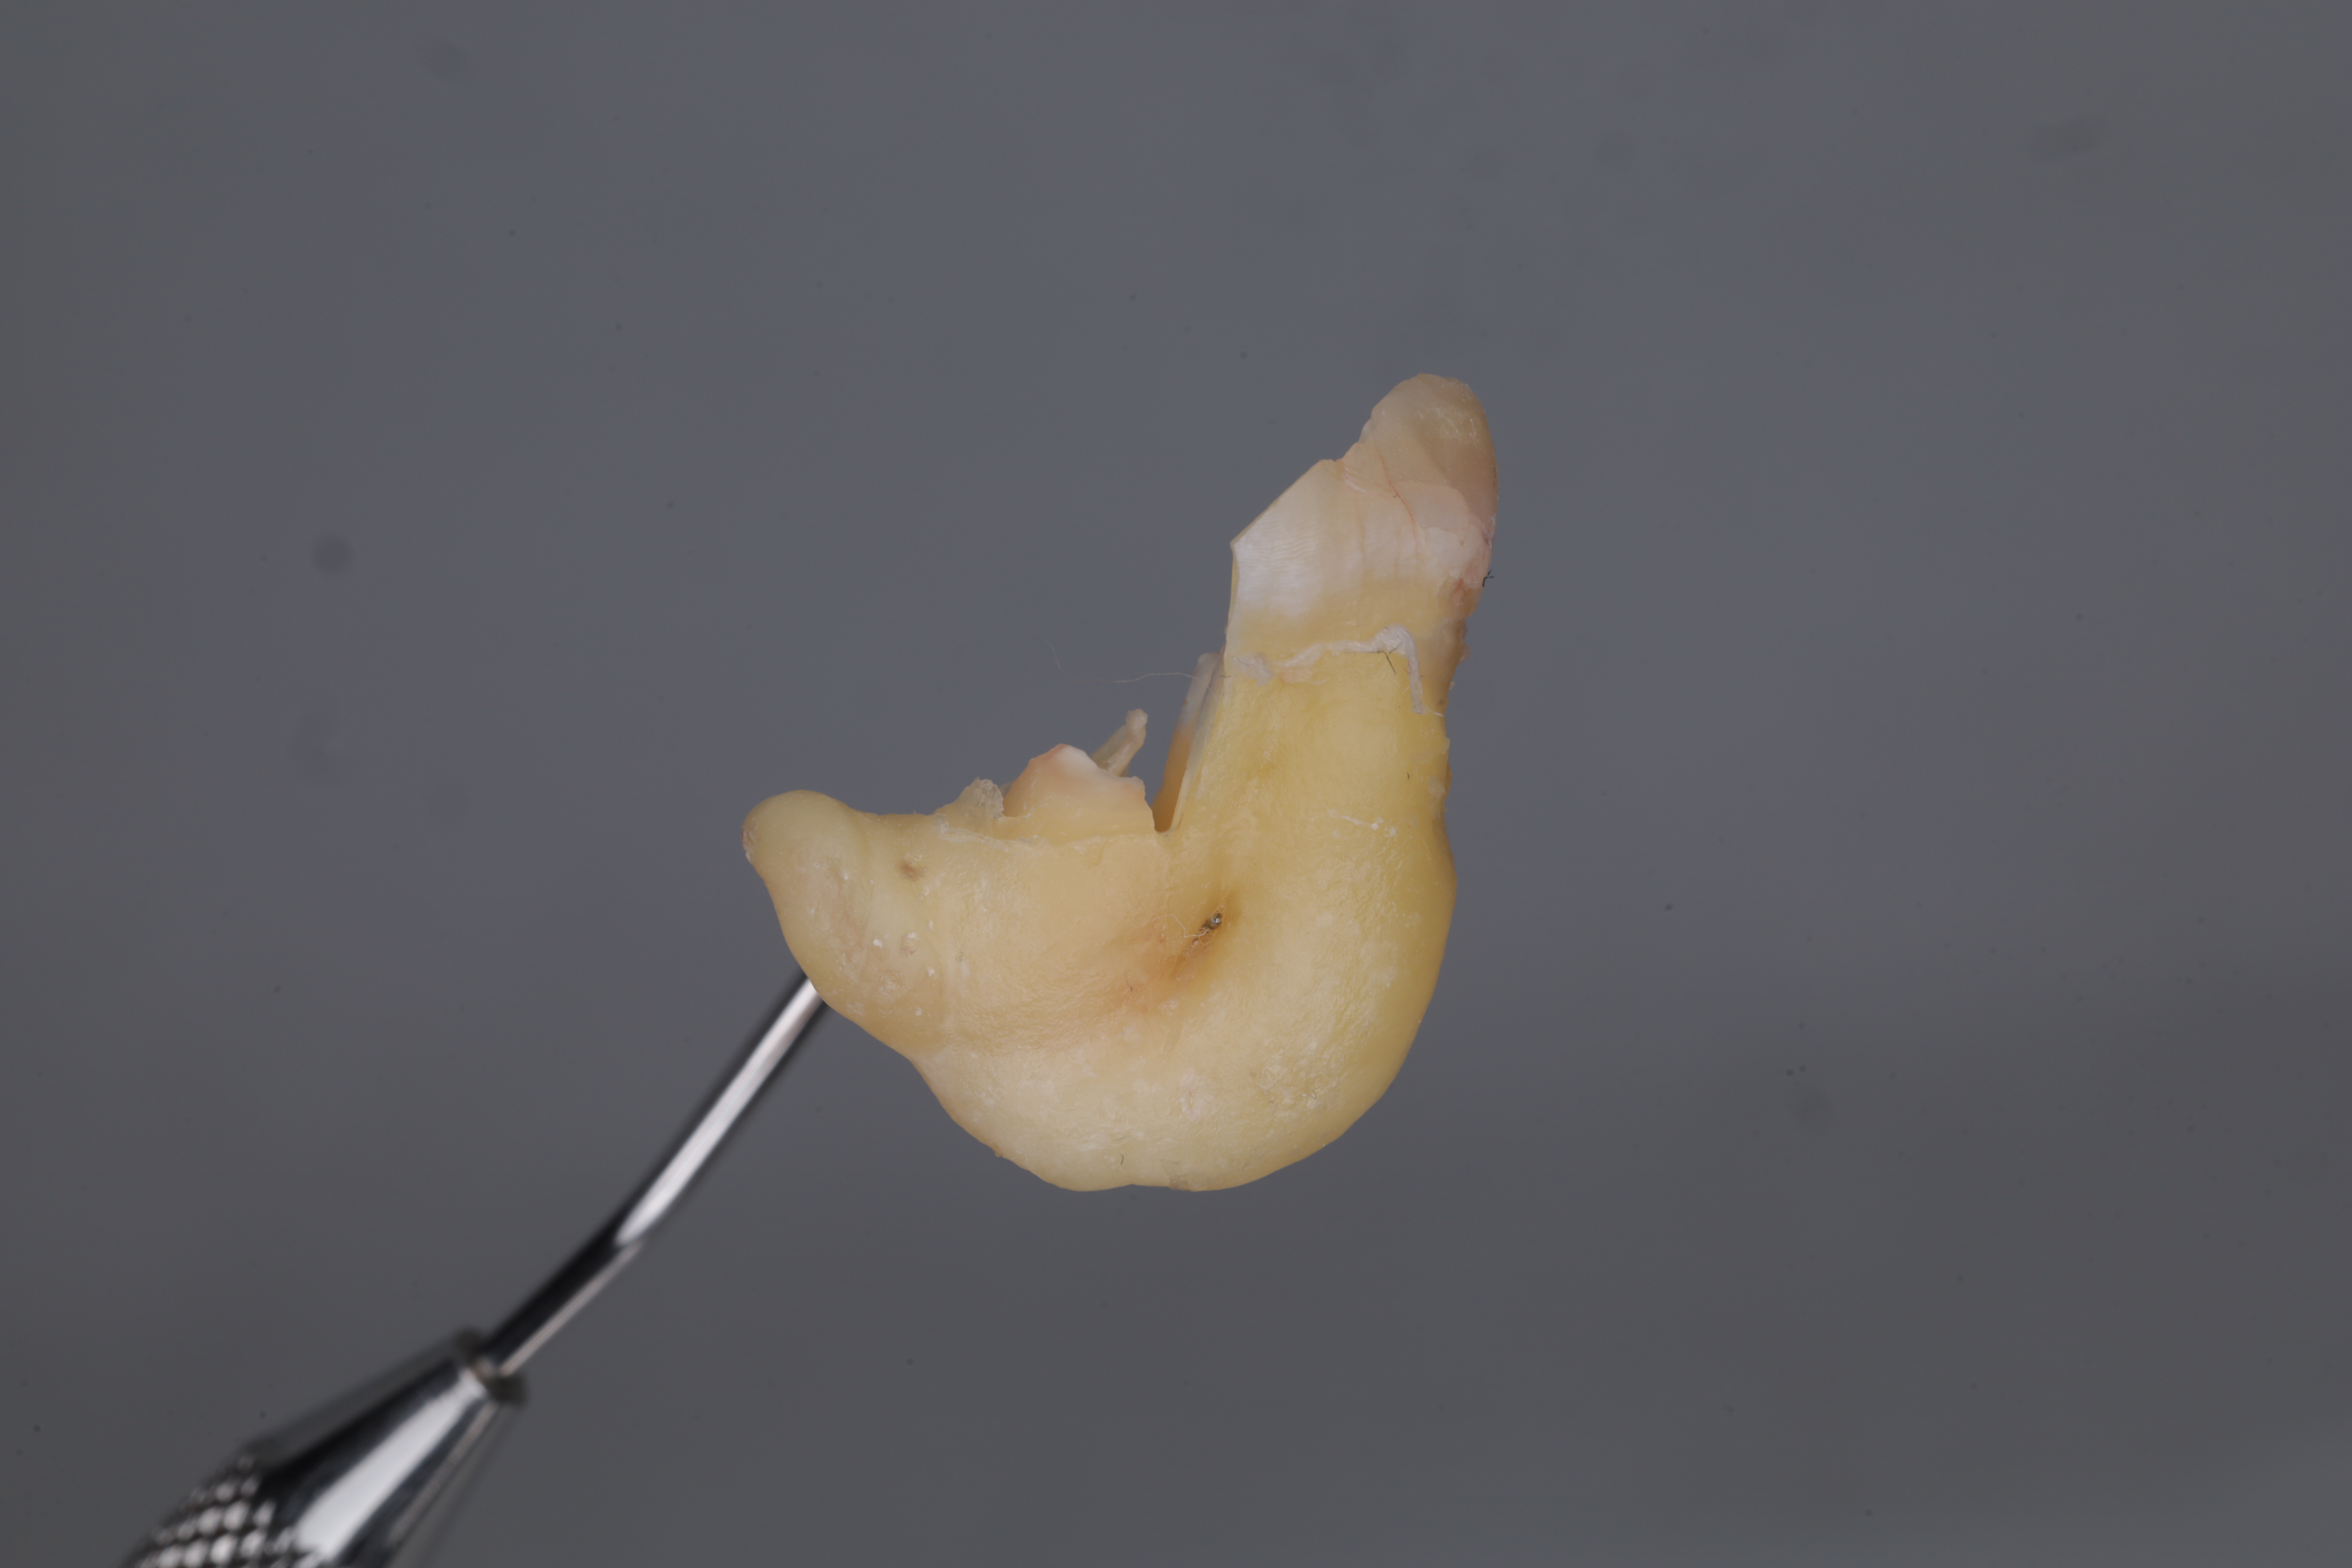

Зуб после удаления с приложенным пародонтальным зондом

После завершения лечения онемения в области нижней губы, подбородка и языка не наблюдалось. Пациент не предъявлял особых жалоб в послеоперационном периоде.